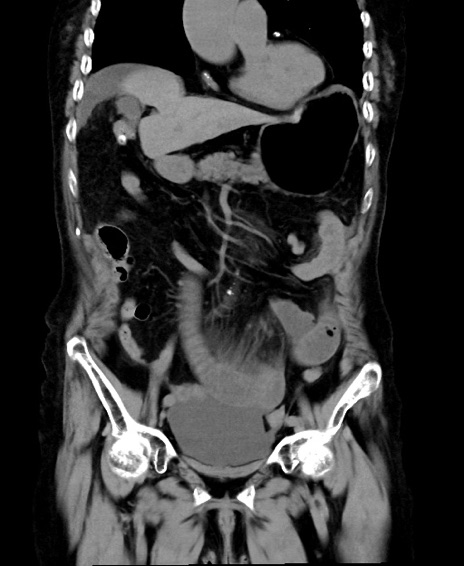

冠状断像

他院CT